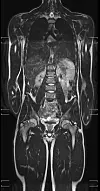

Slik kan en kropp se ut på et MR-bilde. (Foto: Universitetssykehuset Nord-Norge)